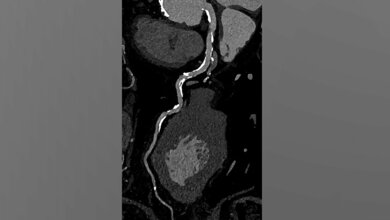

Die Forscherinnen und Forscher betonen, dass sich durch die ultrahochauflösende Photon-Counting-Detektor CTs (PCD-CT) Blutgefäße und Gefäßablagerungen genauer darstellen lassen als bisher. Mithilfe der innovativen Diagnostikmethode, die für eine direkte Umwandlung der auf den Detektor eintreffenden Photonen in elektrische Signale sorgt, konnten in der Studie der Unimedizin Mainz über 50 Prozent der Patientinnen und Patienten in eine niedrigere Krankheitskategorie eingestuft werden. Die Technologie habe das Potenzial, die Patientenversorgung zu verbessern und Gesundheitskosten zu reduzieren. An der Universitätsmedizin Mainz wird das PCD-CT bereits routinemäßig bei Patientinnen und Patienten mit schwerwiegenden Gefäßverkalkungen eingesetzt.

Eine Herzuntersuchung mittels einer Computertomografie gehört zu den diagnostischen Verfahren, die eingesetzt werden, um eine koronare Herzerkrankung zu beurteilen. Diese Bildgebungsmethode stößt bisher jedoch insbesondere bei Betroffenen, bei denen die Ablagerungen bereits stark verkalkt sind, an ihre Grenzen. „Verkalkte Gefäßablagerungen haben eine höhere Dichte und erscheinen durch den sogenannten Calcium-Blooming-Effekt bei der Herz-CT als schwerwiegender, als sie es tatsächlich sind. Dies kann dazu führen, dass die Gefäßverengung, also die Stenose, überschätzt wird“, erklärt Dr. Tilman Emrich, Oberarzt in der Klinik und Poliklinik für diagnostische und interventionelle Radiologie der Universitätsmedizin Mainz und Assistenzprofessor für Radiologie an der Medical University of South Carolina in Charleston.

Eine neue Generation von Computertomografen, die sogenannten PCD-CT, haben im Vergleich zur konventionellen CT eine deutlich verbesserte Bildqualität. Darüber hinaus bieten sie eine bessere räumliche Auflösung. Sie trägt dazu bei, dass zwei benachbarte Strukturen wie das Gefäß und die Ablagerungen genauer unterschieden werden können. „Die neue Technologie könnte ein deutlicher Vorteil für Patientinnen und Patienten sein, deren Stenose durch den Blooming-Effekt überbewertet wurde. Durch die bessere Beurteilung der koronaren Herzerkrankung können sich die Empfehlungen für nachgelagerte Tests erheblich verändern. Dies kann potenziell unnötige invasive Eingriffe reduzieren sowie die Gesundheitskosten senken“, so Emrich.

Die interdisziplinäre kardiologisch-radiologische Forschungsgruppe um Emrich (Radiologie) und Prof. Dr. Michaela Hell (Kardiologie) hat in ihrer Studie 114 Patientinnen und Patienten mit vermuteter oder diagnostizierter koronarer Herzerkrankung mit der PCD-CT untersucht. Sie fanden heraus, dass die ultrahochauflösende CT in vielen Fällen einen geringeren Stenose-Grad ergab als die konventionelle CT. Mit einer Standardauflösung fiel der von den Expertinnen und Experten gemessene Stenosegrad mit einer Verengung von 42 Prozent deutlich größer aus als bei der ultrahohen Auflösung mit 29 Prozent. Mit Hilfe der PCD-CT konnten so rund 54 Prozent der Studienteilnehmenden in eine niedrigere Stenose-Kategorie, die sogenannte CAD-RADS (Coronary Artery Disease Reporting and Data System)-Klasse, eingestuft werden, als sie ursprünglich zugewiesen worden waren. Der Effekt war besonders groß bei Personen, die eine starke Gefäßverkalkung vorwiesen. Bei gemischten und nicht verkalkten Plaques mit geringem Blooming-Effekt stellten die Wissenschaftler/-innen dagegen keine wesentlichen Vorteile der ultrahohen Auflösung fest.